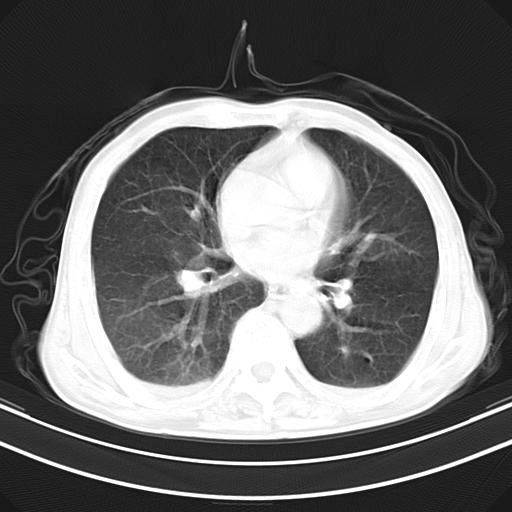

抗炎治疗10天后复查

抗炎治疗10天后复查:右上肺模糊阴影明显减少。